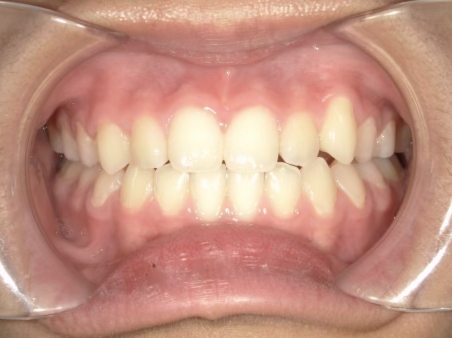

治療中⑨ 中3:14y4m

モノブロック装置で左上八重歯が改善しました

今後、必要によりマルチブラケット法へ移行予定です